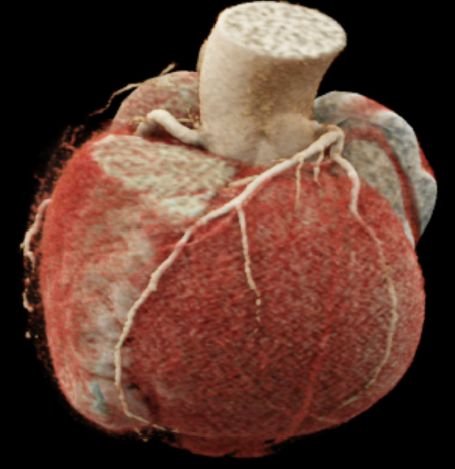

CT Heart

• Cinematic VRT